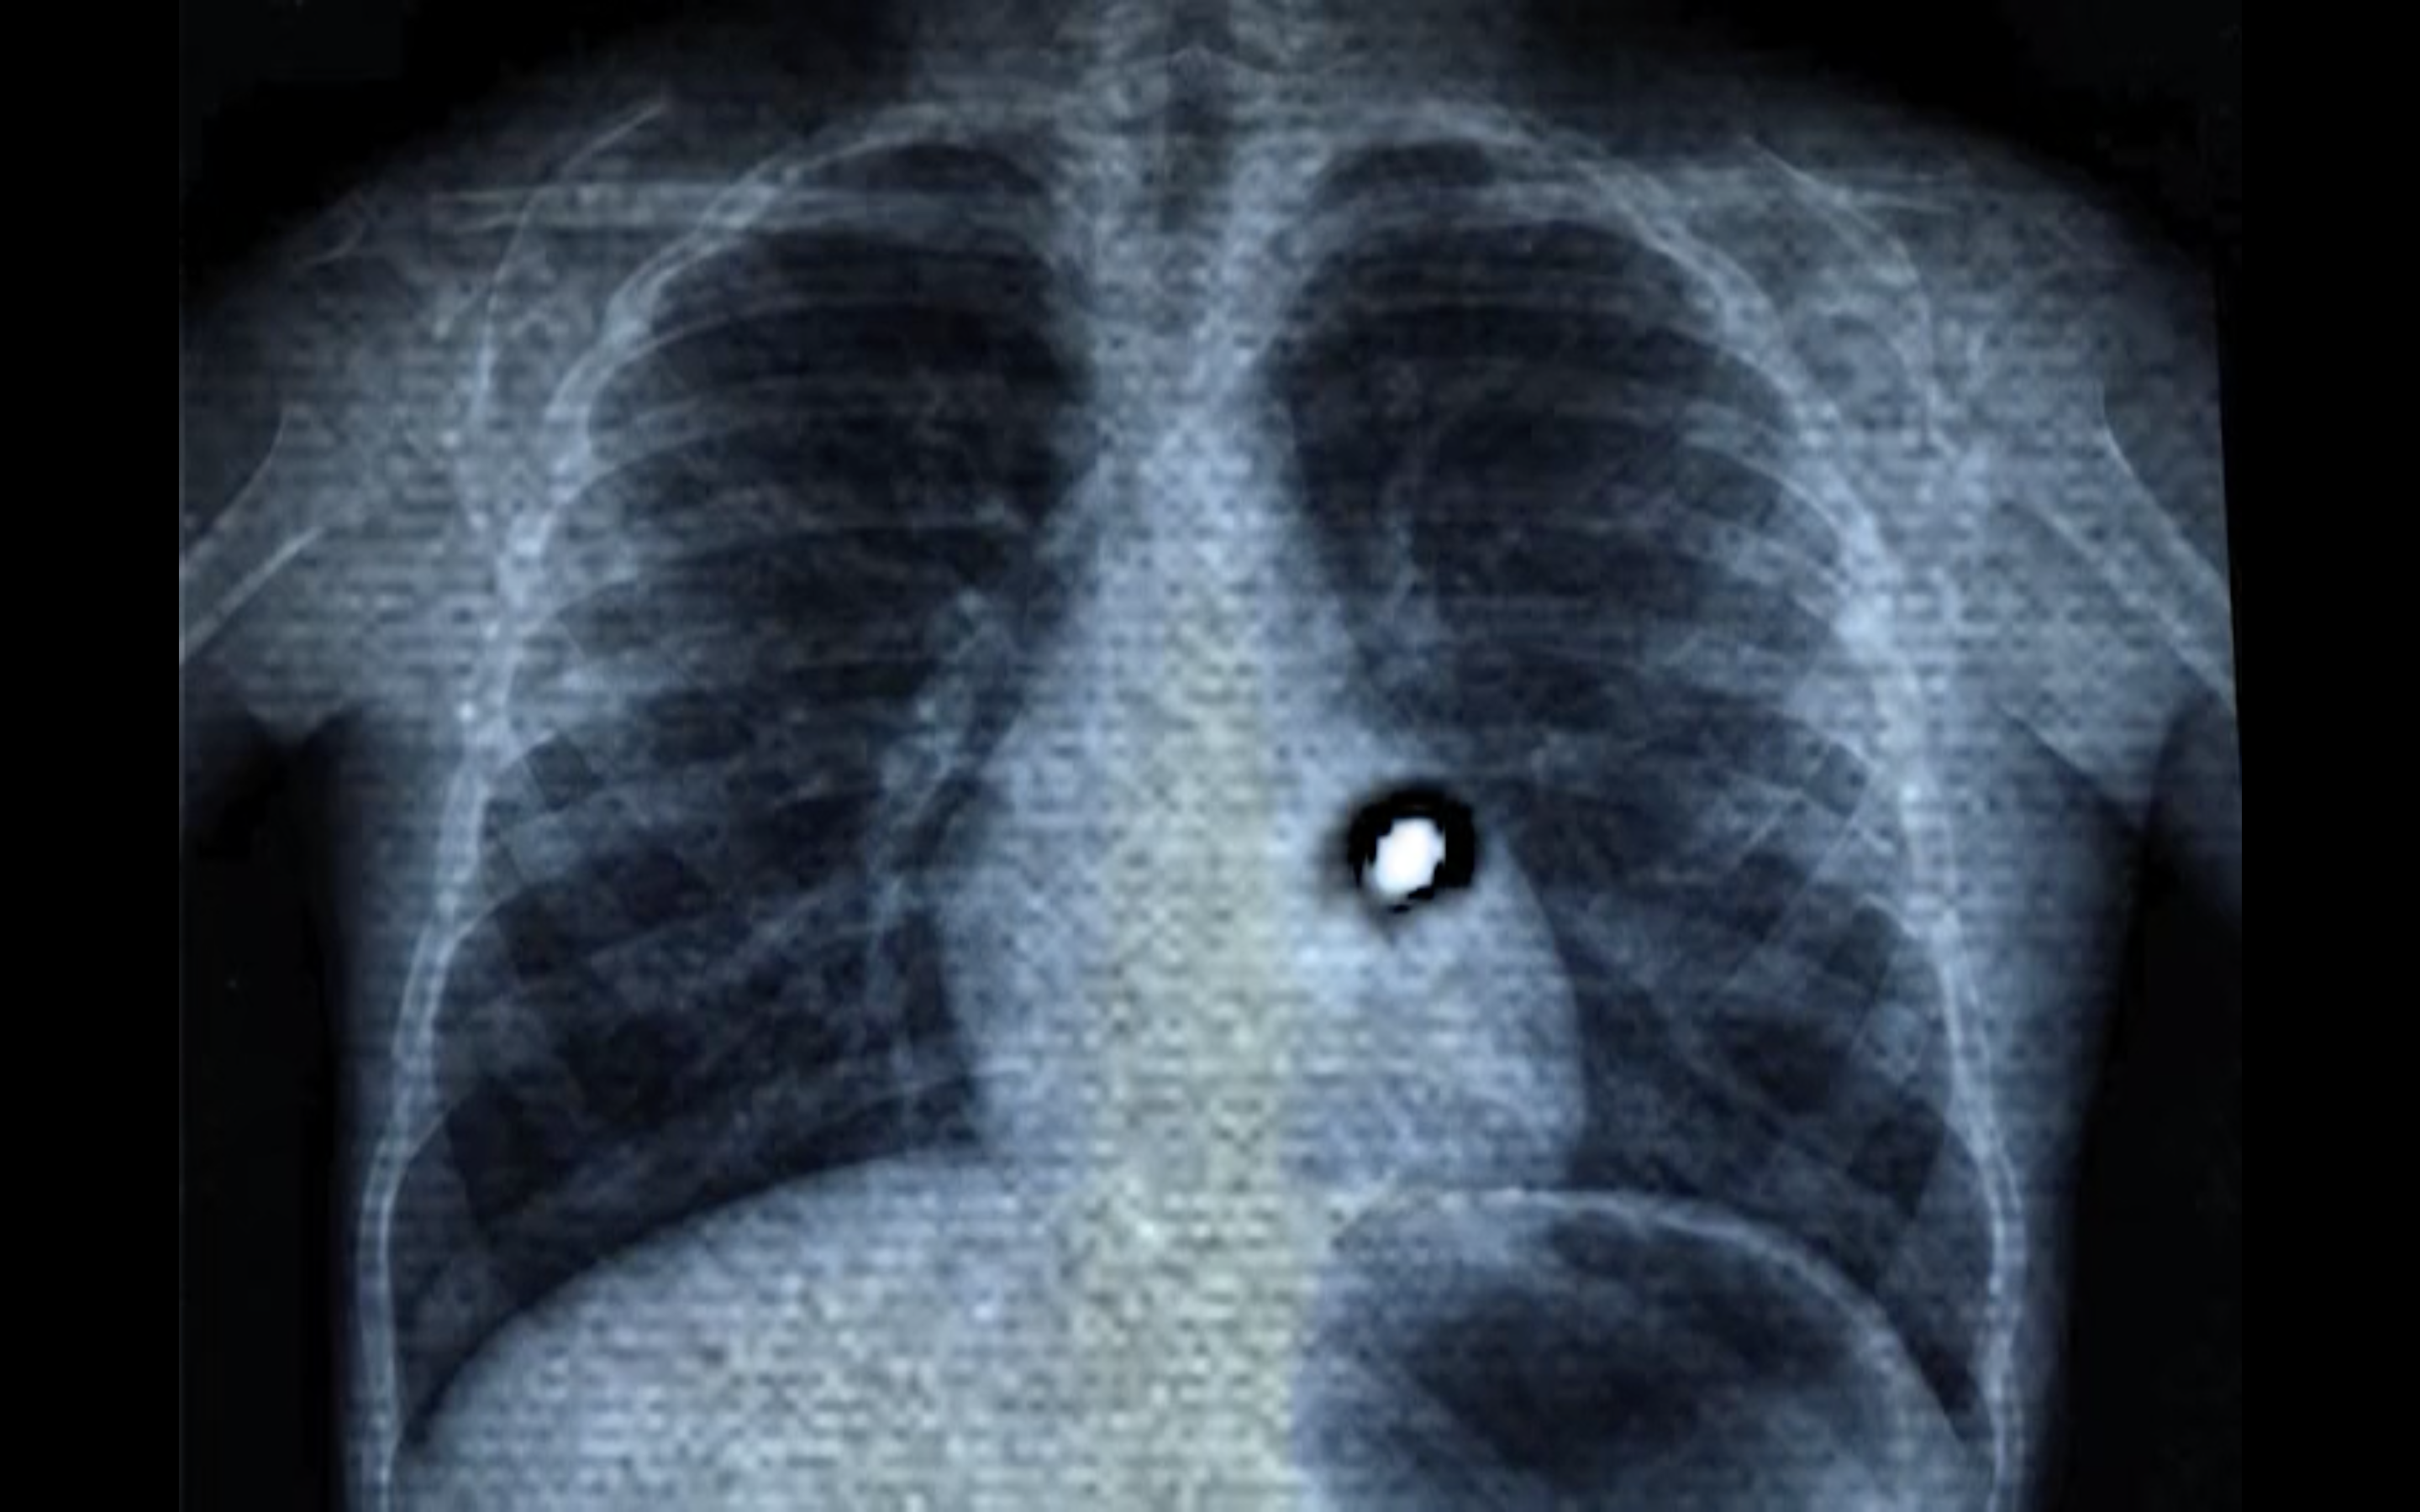

Aram Lee : The work started from an exchange I had with a Chinese Indonesian colleague and friend, Francisca Angela, also a resident at Rijksakademie. Both of us had to undergo a medical exam to diagnose tuberculosis when we arrived in the Netherlands. The exam involves medical imagery: You hold a metal plate to your chest and then hold your breath while an X-ray image is made of the lungs. In my work, I combined the medical image of my own body with the images that I had made under the microscope in collaboration with the immunologist Juan J. Garcia Vallej of the Microbes Laboratory at Amsterdam UMC: we analyzed a water droplet from the basement of the Wereldmuseum Amsterdam that had dripped through the museum’s thick foundations. The test revealed 95 living cultures within that droplet. In spite of all the museum’s efforts to seal its walls and shield their collections from the outside world, thousands of living organisms still managed to infiltrate through the walls in microscopic quantities of water. I was interested in the porosity that became apparent in this process. The museum’s goal of creating a conservation space that could effectively separate inside and outside had failed.

LA : In your film, you overlay footage of the living organisms with the X-ray images of your chest – visually, they inhabit your body, as your lungs are circumspectly examined.

Both my friend and I had to undergo this mandatory examination, because, when I arrived in 2011, Korea was still one of the countries considered “at risk” from tuberculosis. Indonesia is still on the list, but Korea has been removed. Prior to the exam, people of all origins, wait in a room. One begins to perceive oneself and others as bodies whose status is under scrutiny,  present only to establish if they can be labeled healthy and stay, or not. During the exam, you have to stand with a metal plate against your body, and you are asked to breathe in deeply. Then, you have to hold your breath until you have permission to breathe. I experienced the moment as a suspension of my right to breathe, a suspension that would last the time it took them to decide whether the air that I had brought from Korea was threatening to the Netherlands, or not.

LA : X-ray has repeatedly been used in feminist experimental filmmaking, often to refer to the vulnerability of the body, and its “over-exposure” by technology and patriarchy1. In addition to the fragility of the body as displayed in the x-ray images, in your film you bring the images of the moving microbes to your body. Thereby, you operate a shift, whereby your body and the transparent and “overexposed” medical images of your lungs scrutinized with suspicion by a public health service enacting geographical, bodily controls while attributing degrees of potential danger to them, now becomes the support that allows the microbes to move freely. As if confirming the suspicion of the public health authorities, you visually contaminate your body, inscribing living cultures within it that transgress walls without permission. When watching the film, there is an uncertainty whether these are images of disease gaining space in the human body, or whether they are beneficial parts of the body’s vital processes?

LA : Materialist feminism points to the constitutive imbrication of bodies and environments, contradicting strongly the modern isolation of the body or even its parts from the place of its dwelling. The cultural theorist Stacy Alaimo underlines this imbrication with her notion of trans-corporeality, the fact that “the human body is never a rigidly enclosed, protected entity, but is vulnerable to the substances and flows of its environments, which may include industrial environments and their socio/economic forces.”3 She shows that X-ray has served as both a technology of control for dominant classes, and  leverage for environmental justice claims for workers in precarious conditions, notably when demonstrating that diseases are not extrinsic but caused by the conditions of working in mines or with toxic substances. In the use you make of the X-ray image of your own chest, you turn imagery produced within a hygienist perspective with a biopolitical goal into a locus for radical relational co-constitution with others, at your and their existential risk.